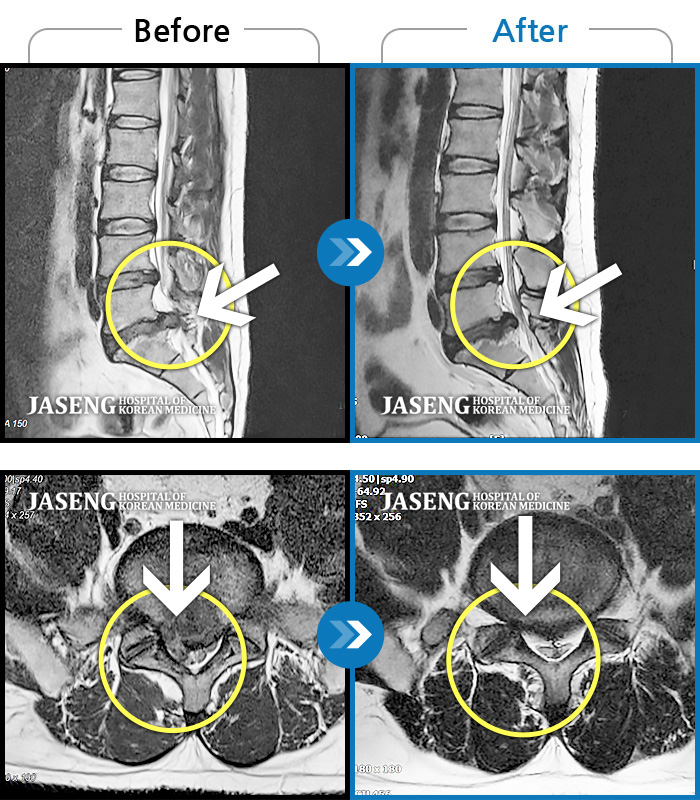

Before

After

환자에게 사전 동의를 받아 동일 조건에서 촬영되었습니다.

개인에 따라 치료 후 부작용이 발생할 수 있으니 의료진과 상담 후 치료를 진행하시기 바랍니다.

허리디스크로 인한 골반 통증

허리 통증, 똑바로 서려고 하거나 걸을 때 양쪽 허벅지와 고관절 시큰거림